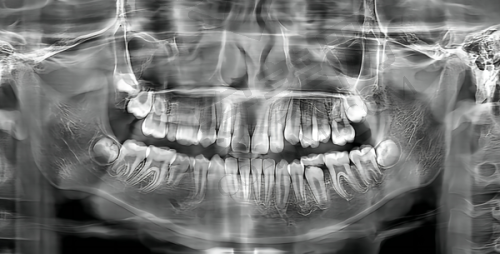

在进行韩国登腾种植牙手术前,患者需要进行全方面的口腔检查,包括X光片、CT等,以确定牙槽骨的条件是否适合种植。患者还需要告知医生自己的病史、过敏史等信息。手术后,患者要遵循医生的嘱咐,注意口腔卫生,避免食用实力强、过烫的食物。要按照规定的时间进行复诊,以便医生及时了解种植体的愈合情况。如果出现疼痛、肿胀等异常情况,应及时与医生联系。